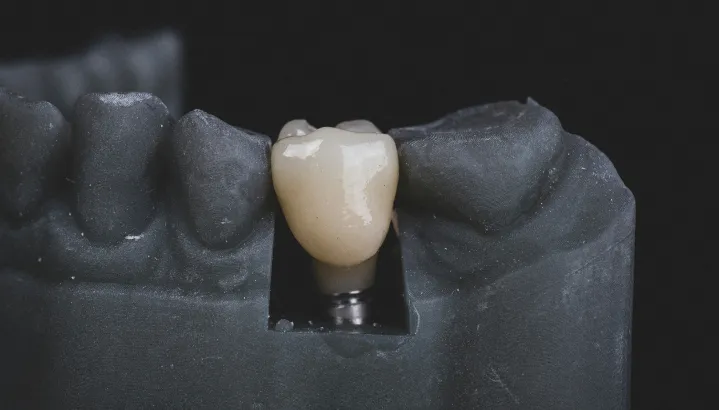

Replacing missing teeth with dental implants at iCube Dental is a precise and technique-sensitive procedure that requires professional expertise and careful planning.

A high-quality titanium implant is securely placed into the jawbone at the site of the missing tooth, creating a strong and stable foundation for a crown or artificial tooth. This design closely mimics the structure and function of a natural tooth, allowing you to chew, bite, and speak comfortably. Dental implants at iCube Dental not only restore your smile but also help maintain jawbone health, prevent bone loss, and improve overall facial structure.